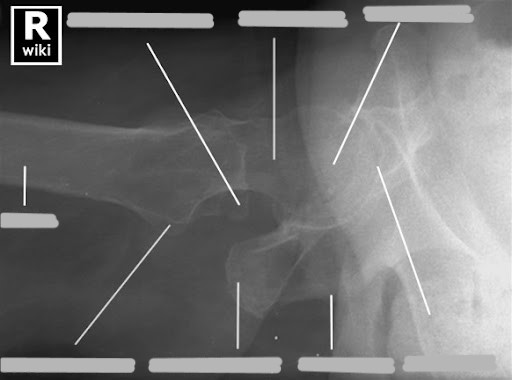

A. ala

B. acetabulum

C. greater trochanter

D. neck

E. lesser trochanter

F. ischial tuberosity

G. superior pubic rami

H. ischial rami